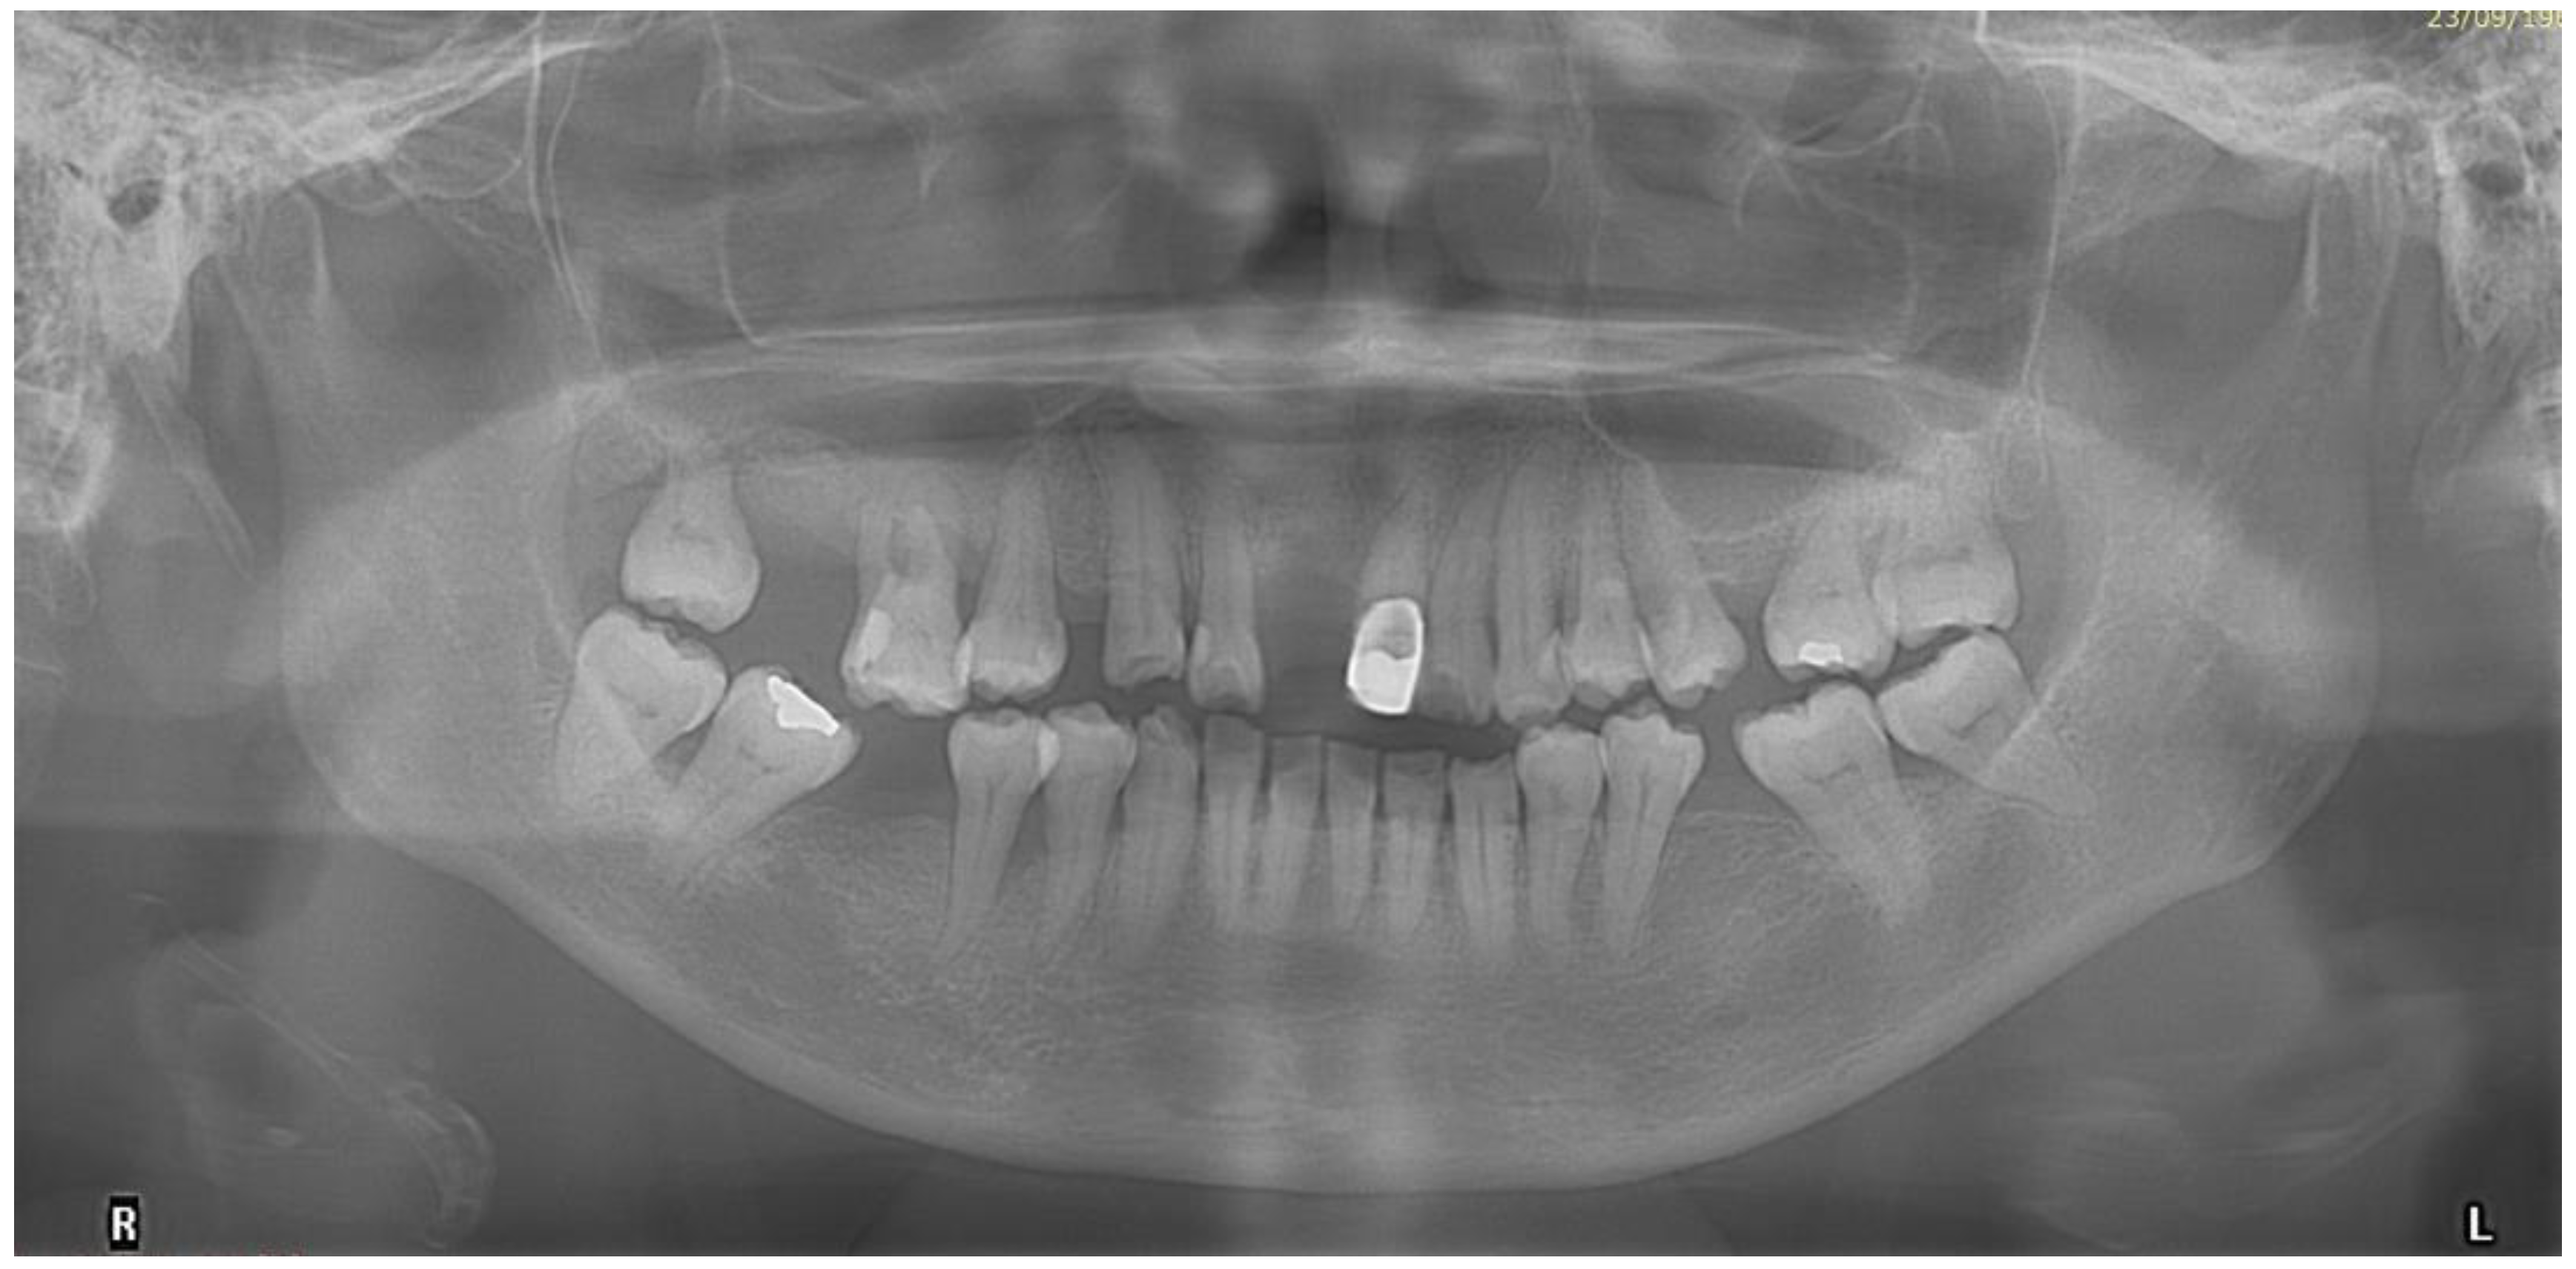

- Before beginning the orthodontic treatment, clinical and radiographic periodontal assessment was performed by the periodontal colleague to confirm that the patient’s periodontal condition had been stabilised after the series of non-surgical and surgical periodontal therapies. Clinical examination included full mouth probing, tooth mobility assessment, and measurement of the amount of gingival recession. The full mouth plaque and bleeding on probing scores were below 25% before beginning the orthodontic treatment [39,40].

- The patient refused to surgically extract the supernumerary tooth as the supernumerary tooth was not associated with any pathology in the patient’s upper jaw for more than 59 years. The decision to keep the supernumerary tooth did affect the planned retraction of upper incisors. This meant that we could not retract the upper incisors as much as we had planned to based on the VTO. As a precaution, radiographs were taken regularly during the orthodontic treatment to ensure that there was no pathology with the supernumerary tooth and the supernumerary tooth did not affect the movement of the upper anterior teeth. As the mid-treatment orthopantomogram (Figure 12) showed that the root apex of tooth 23 was very close to the supernumerary tooth, we decided to stop further retracting the upper teeth.